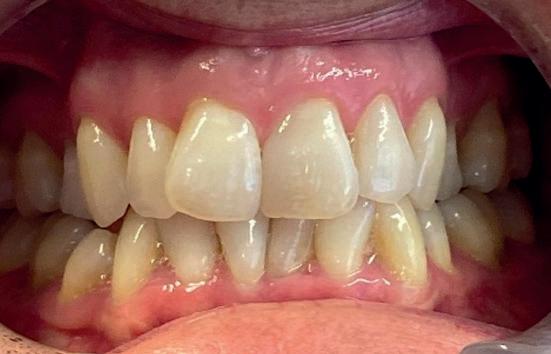

Exposed roots

Gingival recession